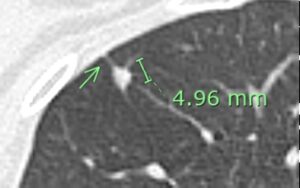

【胸部X線では不明で、胸部CTで見つかった早期肺がんの1例】

○枠の中に肺がんがあるのですが、胸部X線でははっきりしません。

胸部CTでは○枠、矢印の部位に2㎝大の結節を認めました。手術の結果、早期肺がんでした。

このように胸部X線では確認できない、助かる肺がんを胸部CTで見つけることができます。